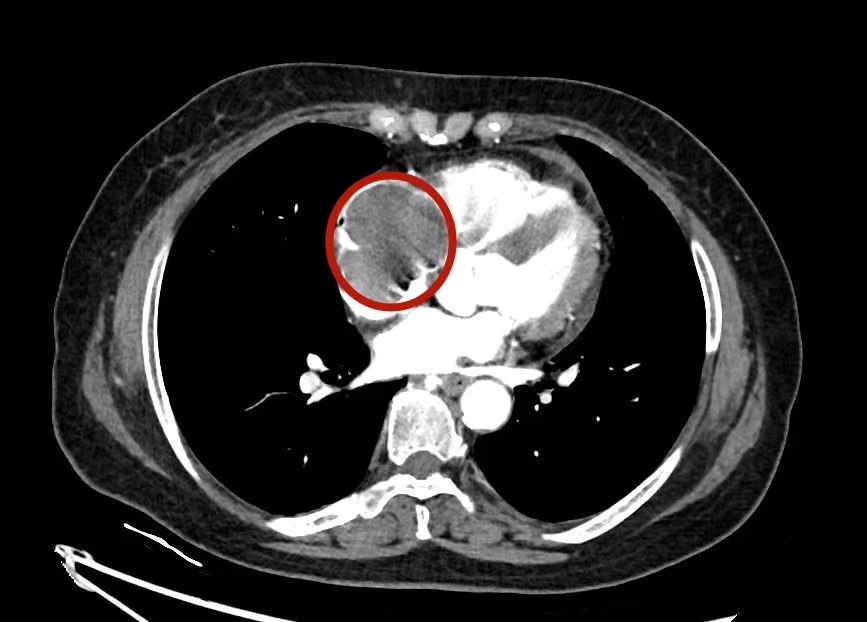

1个月前,柴阿姨突发晕厥,到当地医院检查后发现,导致其晕厥的原因竟然是心脏里长了肿瘤。为进一步明确诊断,她和家人慕名来到上海市胸科医院胸外科就诊。检查结果让医生们心头一紧,患者心脏里肿瘤来自前纵隔,肿块已经像“藤蔓”一样顺着血管长进了心脏,不仅侵犯上腔静脉,还几乎占据了整个右心房!“这种情况非常危险!”胸外科主任医师、科副主任茅腾向家属解释道,“心脏内的瘤栓一旦脱落,可能导致肺栓塞或脑栓塞危及生命。若不尽快手术,任其继续生长,还将导致致命的心脏衰竭。”

面对如此棘手的病情,茅腾与心外科副主任医师李伟立即进行联合会诊。经过全面评估和充分准备,团队制定了细致的手术方案,并与家属进行了深入沟通。手术需要在体外循环下进行,难度和风险都非常大!医生在处理胸腔内和心脏里的肿瘤同时,还要完成大血管重建,对团队的技术水平和配合默契度都是极大考验。